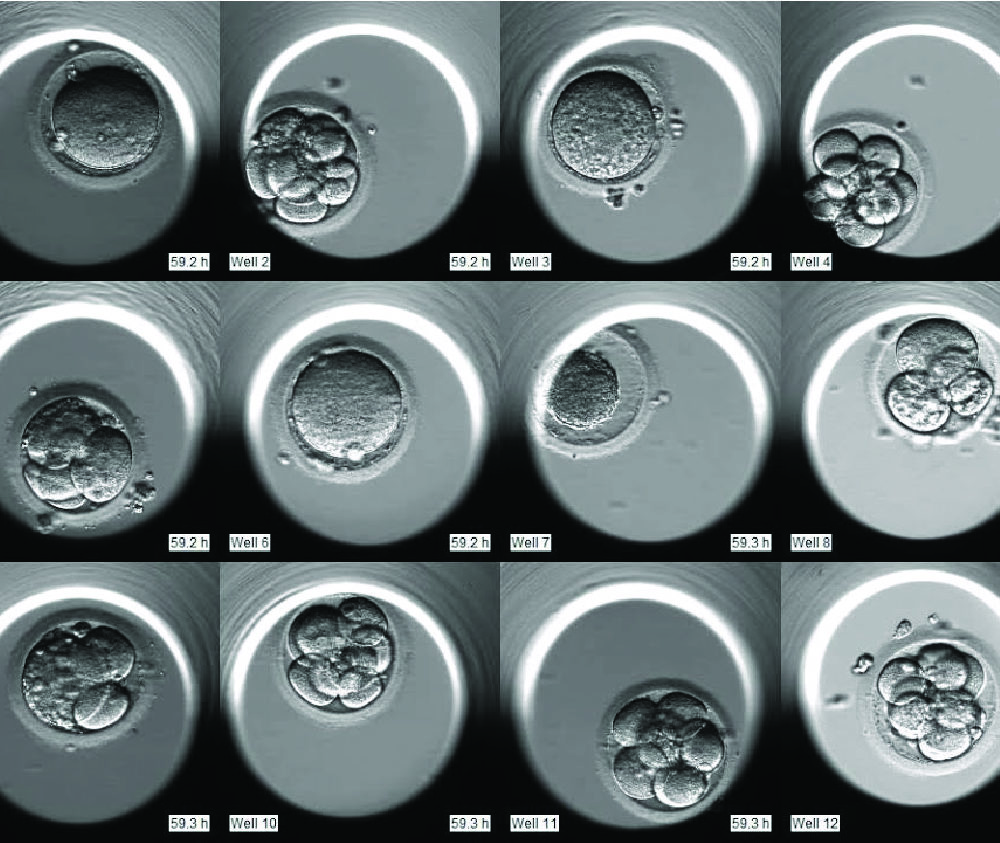

- Непрерывно фиксирует развитие эмбриона

- Делает тысячи микроснимков без извлечения эмбриона

- Формирует видео его роста и деления клеток